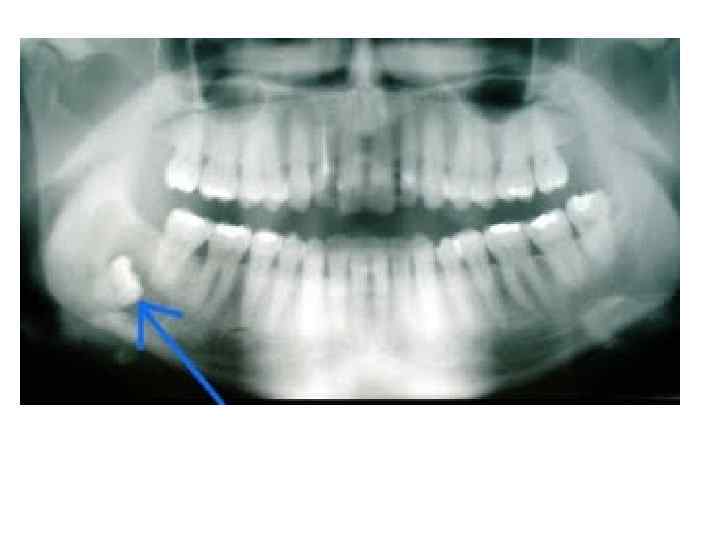

Дистопия – • Это неправильное положе ние в зубном ряду прорезавшегося зуба или аномалийное (смещенное) расположение зуба в челюсти. • Встречаются, но редко, сверхкомплектные зубы Боковая рентгенограмма нижней челюсти. Имеется сверхкомплектный зуб.